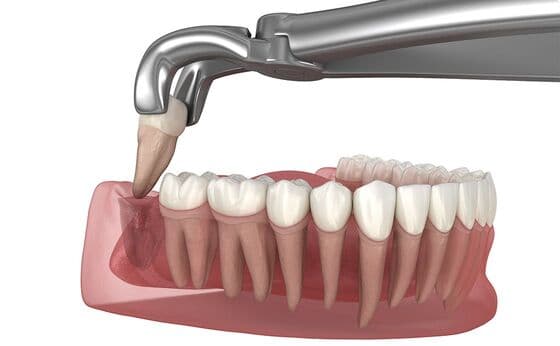

親知らず抜歯について

当院の口腔外科では、親知らずの抜歯を専門的に行っています。抜歯は個々の症例により難易度が異なるため、CTスキャンなどの画像診断を用いて、事前に安全な治療計画を立てます。

痛みの少ない治療:局所麻酔により、できる限り痛みを感じないように治療を行います。

親知らずの生え方と

抜歯の難易度

親知らずは以下の3つの生え方があり、そのタイプにより抜歯の難易度が変わります。

まっすぐに生えている

親知らずが上向きにまっすぐに生えていますが、顎のスペースが足りなければ抜歯するケースもあります。

難易度1

比較的簡単に抜歯できます。

斜めに生えている

親知らずが斜めに生え、手前の歯に当たってすべて表に出ていません。下顎によく見られるタイプです。

難易度2

多くの場合、歯を一部分削り、分割して抜歯します。

水平な状態で埋まっている

親知らずが歯ぐきの中にすべて埋まり、横向きで手前の歯を押している状態です。

難易度3

神経を傷つけないよう注意しながら、歯を分割して抜歯します。当院では口腔外科担当の歯科医師が在籍しているため、難易度の高い抜歯にも対応できます。